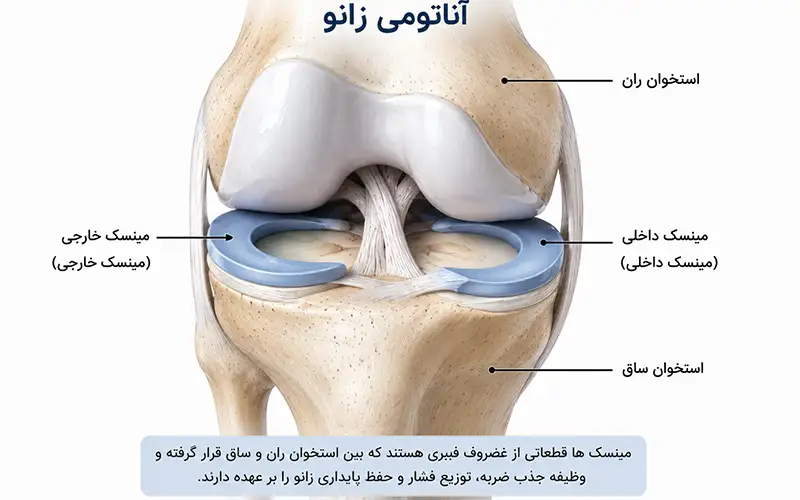

منیسک داخلی زانو ساختاری به شکل حرف C باز دارد و شعاع انحنای آن از منیسک خارجی بیشتر است. منیسک داخلی زانو دارای دو بخش به نام شاخ قدامی و شاخ خلفی است.

شاخ خلفی منیسک داخلی پهنتر از شاخ قدامی بوده و در قسمت جلویی رباط صلیبی خلفی (PCL) به استخوان تیبیا متصل میشود. شاخ قدامی نیز در فاصله حدود ۶ تا ۸ میلیمتر جلوتر از رباط صلیبی قدامی (ACL) به تیبیا اتصال دارد.

قسمت محیطی منیسک داخلی به کپسول داخلی مفصل زانو متصل است و این اتصال از طریق لیگامان کورونری به لبه فوقانی استخوان تیبیا انجام میشود.

منیسک خارجی شکلی نزدیک به C بسته دارد و شعاع آن کمتر از منیسک داخلی است. این منیسک نسبت به نوع داخلی، سطح وسیعتری از بخش فوقانی استخوان تیبیا را میپوشاند.

منیسک خارجی از اطراف به کپسول مفصلی خارجی زانو متصل است. شاخ قدامی آن به ناحیه جلویی برجستگیهای بینکندیلی متصل میشود و شاخ خلفی نیز در قسمت خلفی همین برجستگیها و در جلوی محل اتصال شاخ خلفی منیسک داخلی قرار دارد.